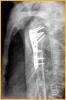

锁定板治疗老年人骨质疏松性移位的肱骨近端骨折

患者女,72岁,诊断为:肱骨近端骨折。

行肱骨近端锁定型钉板(PHILOS)固定术,手术过程:采用全麻或斜方肌阻滞麻醉,用沙滩椅体位,术中肱骨头复位后,用二至三枚克氏针临时固定保持复位,并使其余骨折块复位,然后透视确认复位质量。用5号不可吸收缝线将大小结节缝合修复,再选用适当长度的锁定钉板置于肱骨近端和肱骨干的外侧面。注意避免将钢板放置的过高以致成角螺钉的位置不合适而不能达到最佳骨接触。可用一枚非锁定螺钉固定于肱骨干上可使钢板远近端滑动调整位置。然后使用导向器上锁定螺钉使钢板和螺钉一体化。固定完成后再次透视确认无误,处理好软组织后逐层关闭切口。